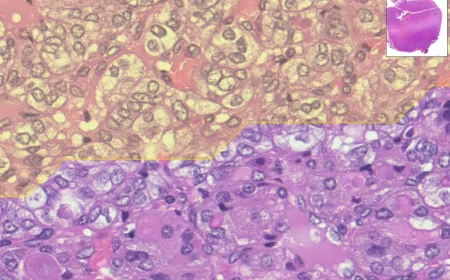

I risultati mostrano che Dysosmobacter welbionis è associato a un quadro di buona salute metabolica ed epatica. In particolare, la sua assenza o ridotta rappresentazione nell’intestino sembra essere una caratteristica di soggetti affetti da steatosi epatica associata a disfunzione metabolica o da fibrosi epatica avanzata; viceversa, la sua presenza è associata a un miglioramento di possibili disturbi metabolici.

«Lo studio si è concentrato sul potenziale ruolo protettivo di questo batterio intestinale per la salute del fegato: la sua assenza o ridotta rappresentazione nell'intestino sembra essere una caratteristica di soggetti affetti da steatosi epatica associata a disfunzione metabolica, o presentanti una fibrosi epatica avanzata; viceversa, la sua presenza è associata a un miglioramento di possibili disturbi metabolici».